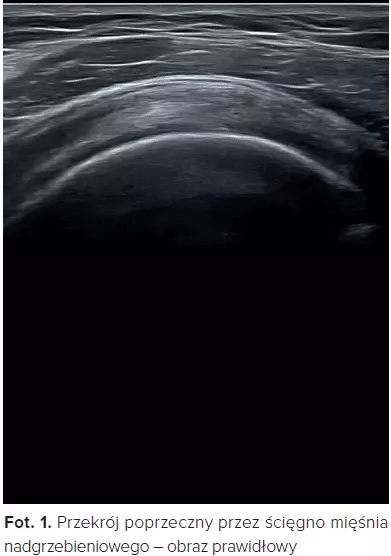

Od kilku już lat ultrasonografia narządu ruchu w Polsce znajduje zastosowanie jako bardzo praktyczne narzędzie zarówno do szybkiej diagnostyki uszkodzeń urazowych mięśni, ścięgien i więzadeł, przesiewowego badania stopnia zmian zwyrodnieniowych

i zapalnych stawów, jak również celowanej rehabilitacji pod postacią sonofeedbacku. Na początek kilka obrazów uszkodzeń ścięgien stożka rotatorów stawu ramiennego.